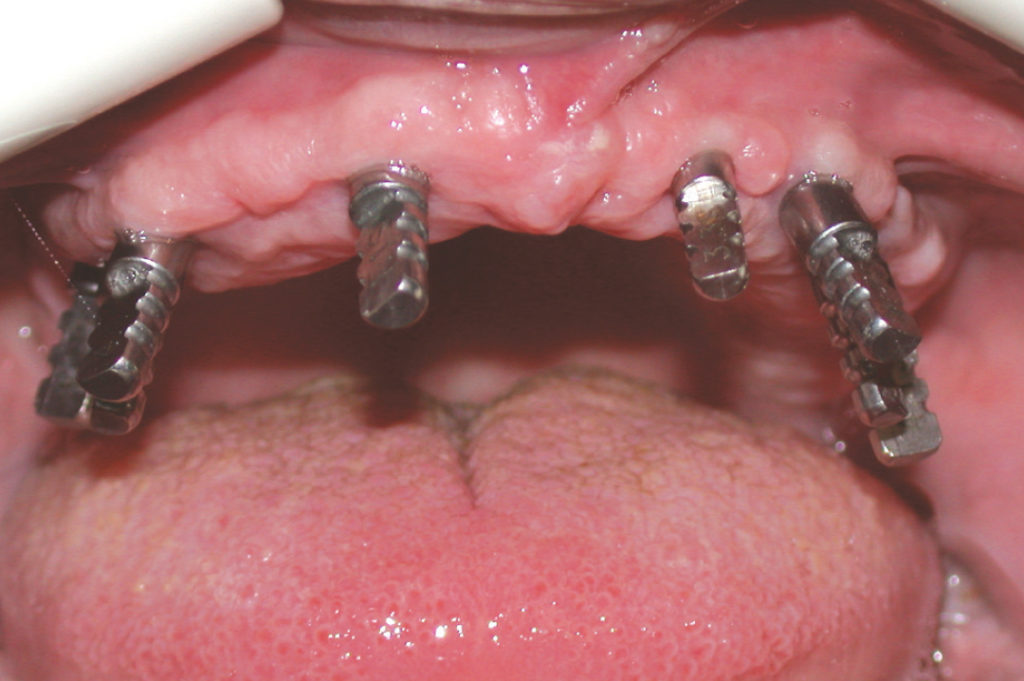

View of transfers positioned in the lower implants for impression taking